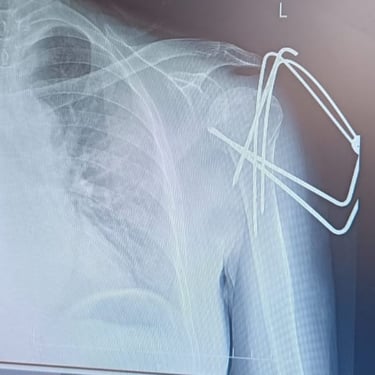

Limb reconstruction and complex trauma surgery

Trauma (Fractures)

Orthopedic trauma (fractures) refers to injuries to the musculoskeletal system, like bones, joints, and muscles, often from accidents, falls, or sports